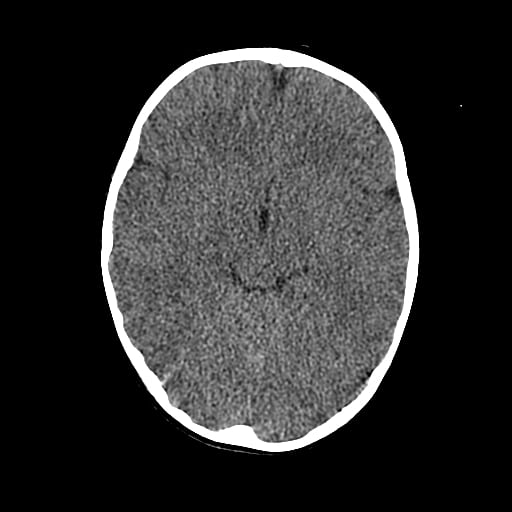

Age: 1

Sex: Male

Indication: Fall